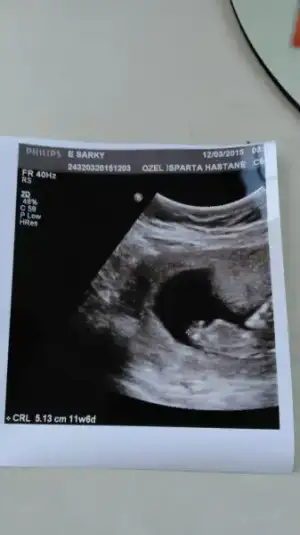

rus cinsiyet takvimini denemedim canım. çünkü eşim neredeyse her yıl kan bağışında bulunur. kan bağışı yapan çiftlerde bu takvim tutmuyormuş. benim de daha 10 hafta dolmadı. ultrason fotoları atayım ama daha çok küçük pek bir şey anlaşılacağını düşünmüyorum ama yine de bakarsanız sevinirimBende çin takvimi, rus cinsiyet takvimi ,biyoloji takvimde denedim kiz diyor.. arti meyve hic sevmem tatli sevmem tuzlu eksi hic birinide sevmem.. netteki butun belirtilere gore alyans yuzuge kadar hepsinde kiz cikiyor...usg resmindede sagda yani ordada kiz.. ki bende tecrubeli bir anne olarak kiz diyorim. 2 hafta sonra gidecem dr. Bakalim o ne diyecek :))))

Erkek gibi canim :)rus cinsiyet takvimini denemedim canım. çünkü eşim neredeyse her yıl kan bağışında bulunur. kan bağışı yapan çiftlerde bu takvim tutmuyormuş. benim de daha 10 hafta dolmadı. ultrason fotoları atayım ama daha çok küçük pek bir şey anlaşılacağını düşünmüyorum ama yine de bakarsanız sevinirim

hamileliğimden beri ilk defa alttan muayene oldum. çok korktum. vajinal ultrason da oturmuş gibi göünüyor. kafası üstte alttan kollar gözükmüş. karından ultrasonda sanki bebek daha güzel görünüyor yandan bir görüntü oluyor. hayırlısı bakalım. sağol canım.Erkek gibi canim :)